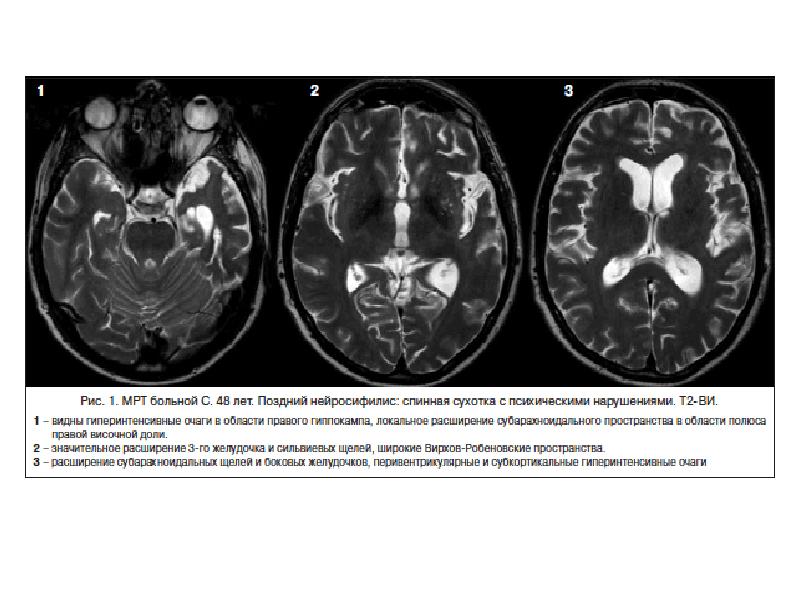

- 14. Поздний нейросифилис паренхиматозный-дистрофический >5 лет Поздний зрачковый моносиндром миоз, анизокория, деформация зрачков,

- 15. Поздний нейросифилис Спинная сухотка (tabes dorsalis) Классические стадии: б)

- 16. Поздний нейросифилис Спинная сухотка (tabes dorsalis) Классические стадии: в)